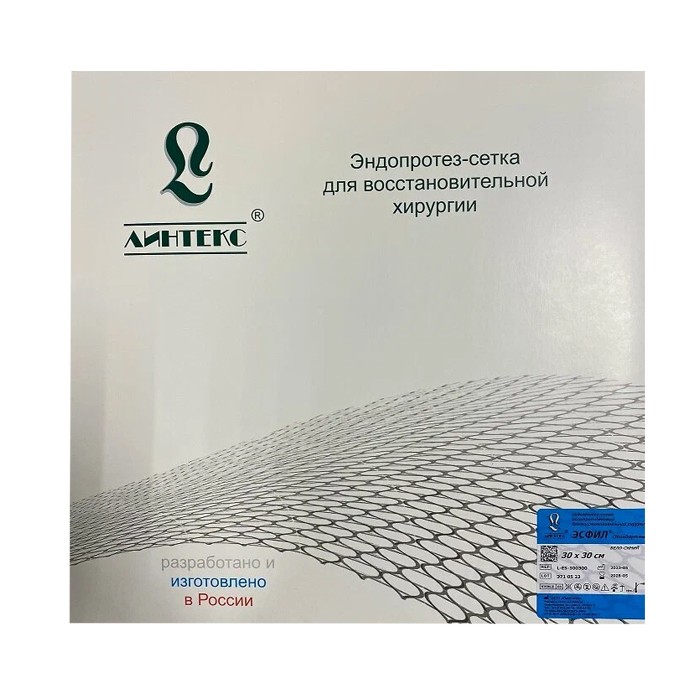

Эндопротез-сетка (сетка хирургическая) полипропиленовый для восстановительной хирургии ЭСФИЛ тяжелый, 30х10 см, Линтекс

Эндопротез-сетка полипропиленовая ЭСФИЛ тяжелый для восстановительной хирургии

| Наименование товара | Эндопротез-сетка (сетка хирургическая) полипропиленовая для восстановительной хирургии ЭСФИЛ тяжелый |

| Бренд / Производитель | Линтекс (Россия) |

| Размер | 30 см x 10 см |

| Стерильность | Стерильно, индивидуальная упаковка |

| Назначение | Для ненатяжной герниопластики и реконструктивных операций |